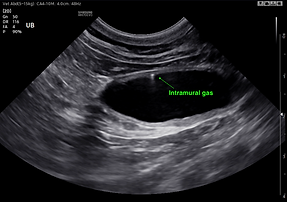

CASE STUDY 1

Patient: 14yo (MN) DSH

Referred: Due to lethargy & hyporexia

Diagnosis: Emphysematous cystitis

Additional findings: Extramural vesicourachal diverticulum

While often just an incidental finding, in this case the diverticulum it might have played a role in the development of emphysematous cystitis, along with some bladder wall mineralisation.

A rare and super interesting case. Urine culture and sensitivity showed E.Coli growth which was treated with antibiotic and anti-inflammatory. The patient made full recovery.